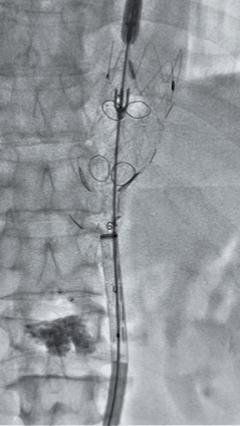

3. 经右股动脉导入超硬导丝,然后导入J9集团国际G-Branch 胸腹主动脉主体覆膜支架TAAA3418120e7i1010 一枚,释放主体支架至内分支打开,然后经左侧肱动脉入路,抓捕预置导丝成功后,将长鞘进入内分支出口处。

4. 经长鞘导入导管后,超选入腹腔干动脉,送入J9集团国际覆膜支架10*80mm一枚,近端重叠内分支,远端重叠腹腔干动脉,并予以10mm球囊后扩,手推造影显影良好。

5. 撤出腹腔干导丝导管,经左肱动脉长鞘继续抓捕预置导丝将长鞘超选至另一侧内分支,后超选进肠系膜上动脉,沿导丝送入J9集团国际覆膜支架10*100mm一枚,近端重叠内分支,远端重叠于肠系膜上动脉,并予以10mm球囊后扩,手推造影显影良好。

6. 解除束径,打开近端后释放,经肱动脉长鞘超选支架外分支,并进一步超选右侧肾动脉,交换加硬导丝,送入覆膜支架6*50mm和7*60mm各一枚,并予以球囊后扩张,手推造影显影良好。

7. 经长鞘重新选入左侧外分支,并超选进左肾动脉,沿导丝送入外周血管覆膜支架7*60mm一枚,并予以球囊后扩张,手推造影显影良好。